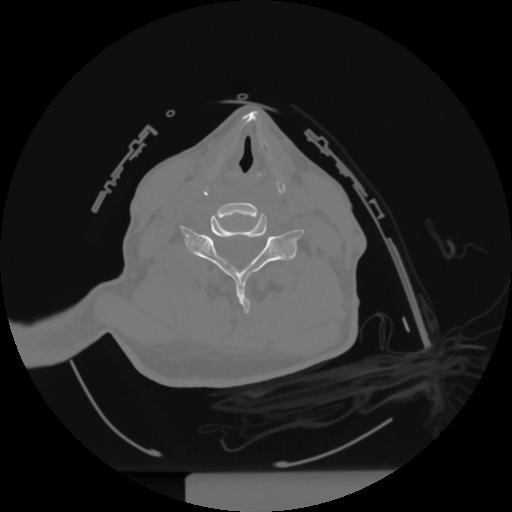

12 P.BLANDAS,,Vol,0.5,P.BLANDAS,,